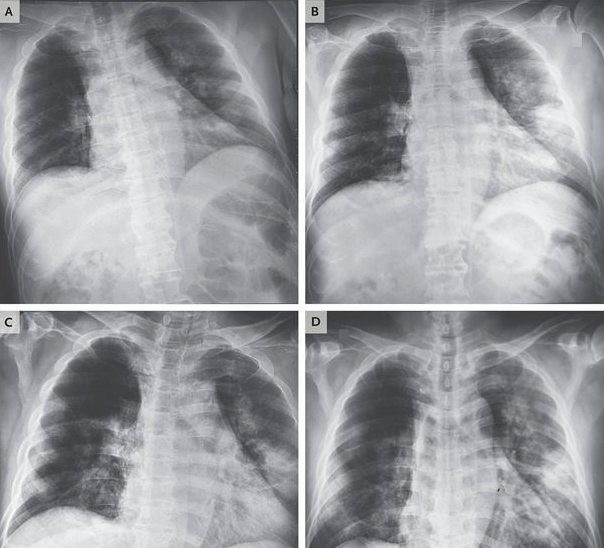

Even a layperson can tell that something is wrong with these lungs. Experts from the Radiological Society of North America (RSNA) published X-ray images of patients who died from the coronavirus, and it’s not a pleasant sight. The lungs are full of white spots — the so-called ground-glass density, where air spaces become partially filled. This then causes severe breathing difficulties.

American scientists have mapped exactly how the more severe form of the coronavirus affects the lungs. They even published X-rays of patients who died from the coronavirus.

You don’t have to be a doctor to recognize that something is wrong with the lungs in the picture. They are covered with a large number of white spots of various sizes. These are by no means a natural occurrence.

This is the so-called ground-glass density.

Air spaces in the lungs become filled, which then causes infected patients to suffer acute respiratory distress, lung pain, and other problems.